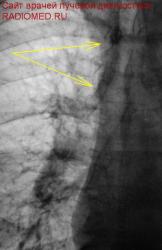

Очень смутило перибронхиальное уплотнение, помеченное жёлтыми стрелками.

3.jpg